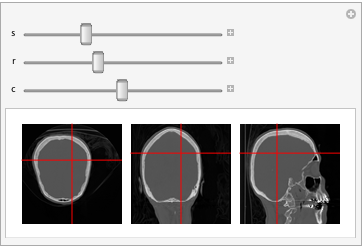

Плоскостные срезы объёмного изображения

Срезы трёхмерного изображения тремя ортогональными плоскостями.